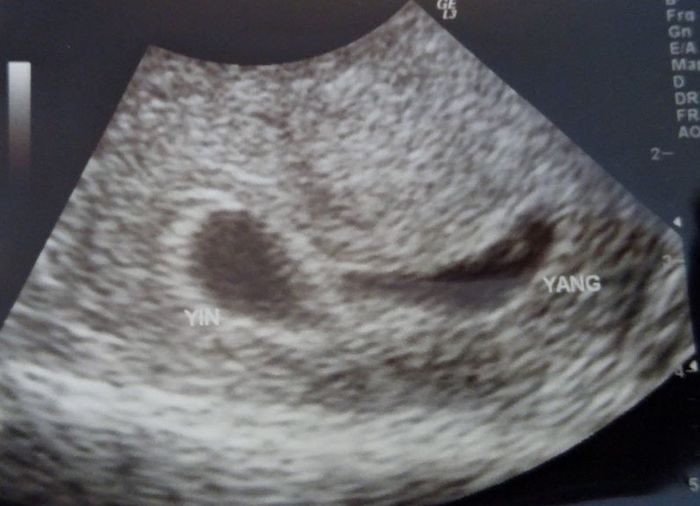

What Does an Ultrasound Look like at 6 Weeks Pregnant With Twins?

Yes! You’d need to have an ultrasound at 6 weeks to confirm a twin pregnancy. Your twin belly at 6 weeks may not look like much of a belly at all, so getting in to your doctor for an ultrasound is key to find out if you’re really having twins.